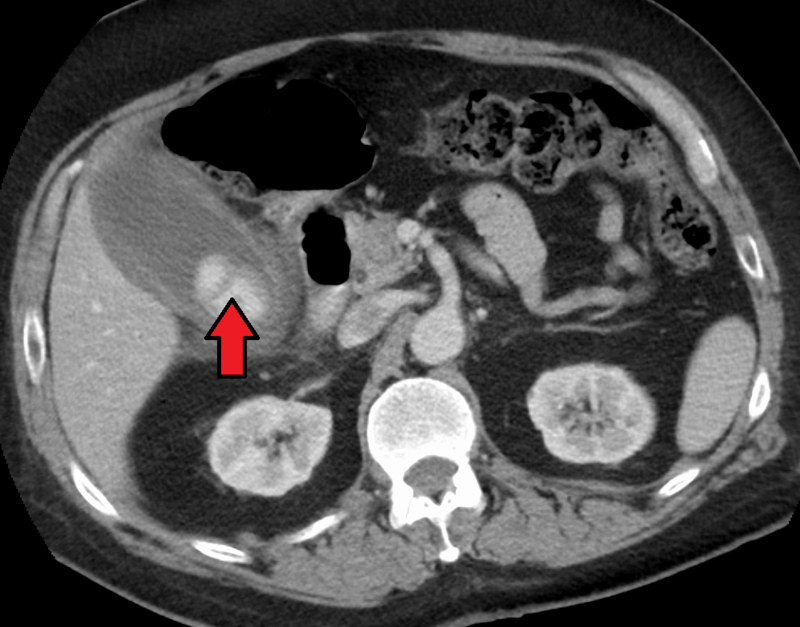

There is a higher prevalence of choledocholithiasis (stone in biliary ducts) in ascending cholangitis.

Ascending cholangitis is a bacterial infection of the bile ducts.

Ascending cholangitis is typically brought on by an escalating gram-negative intestinal infection.